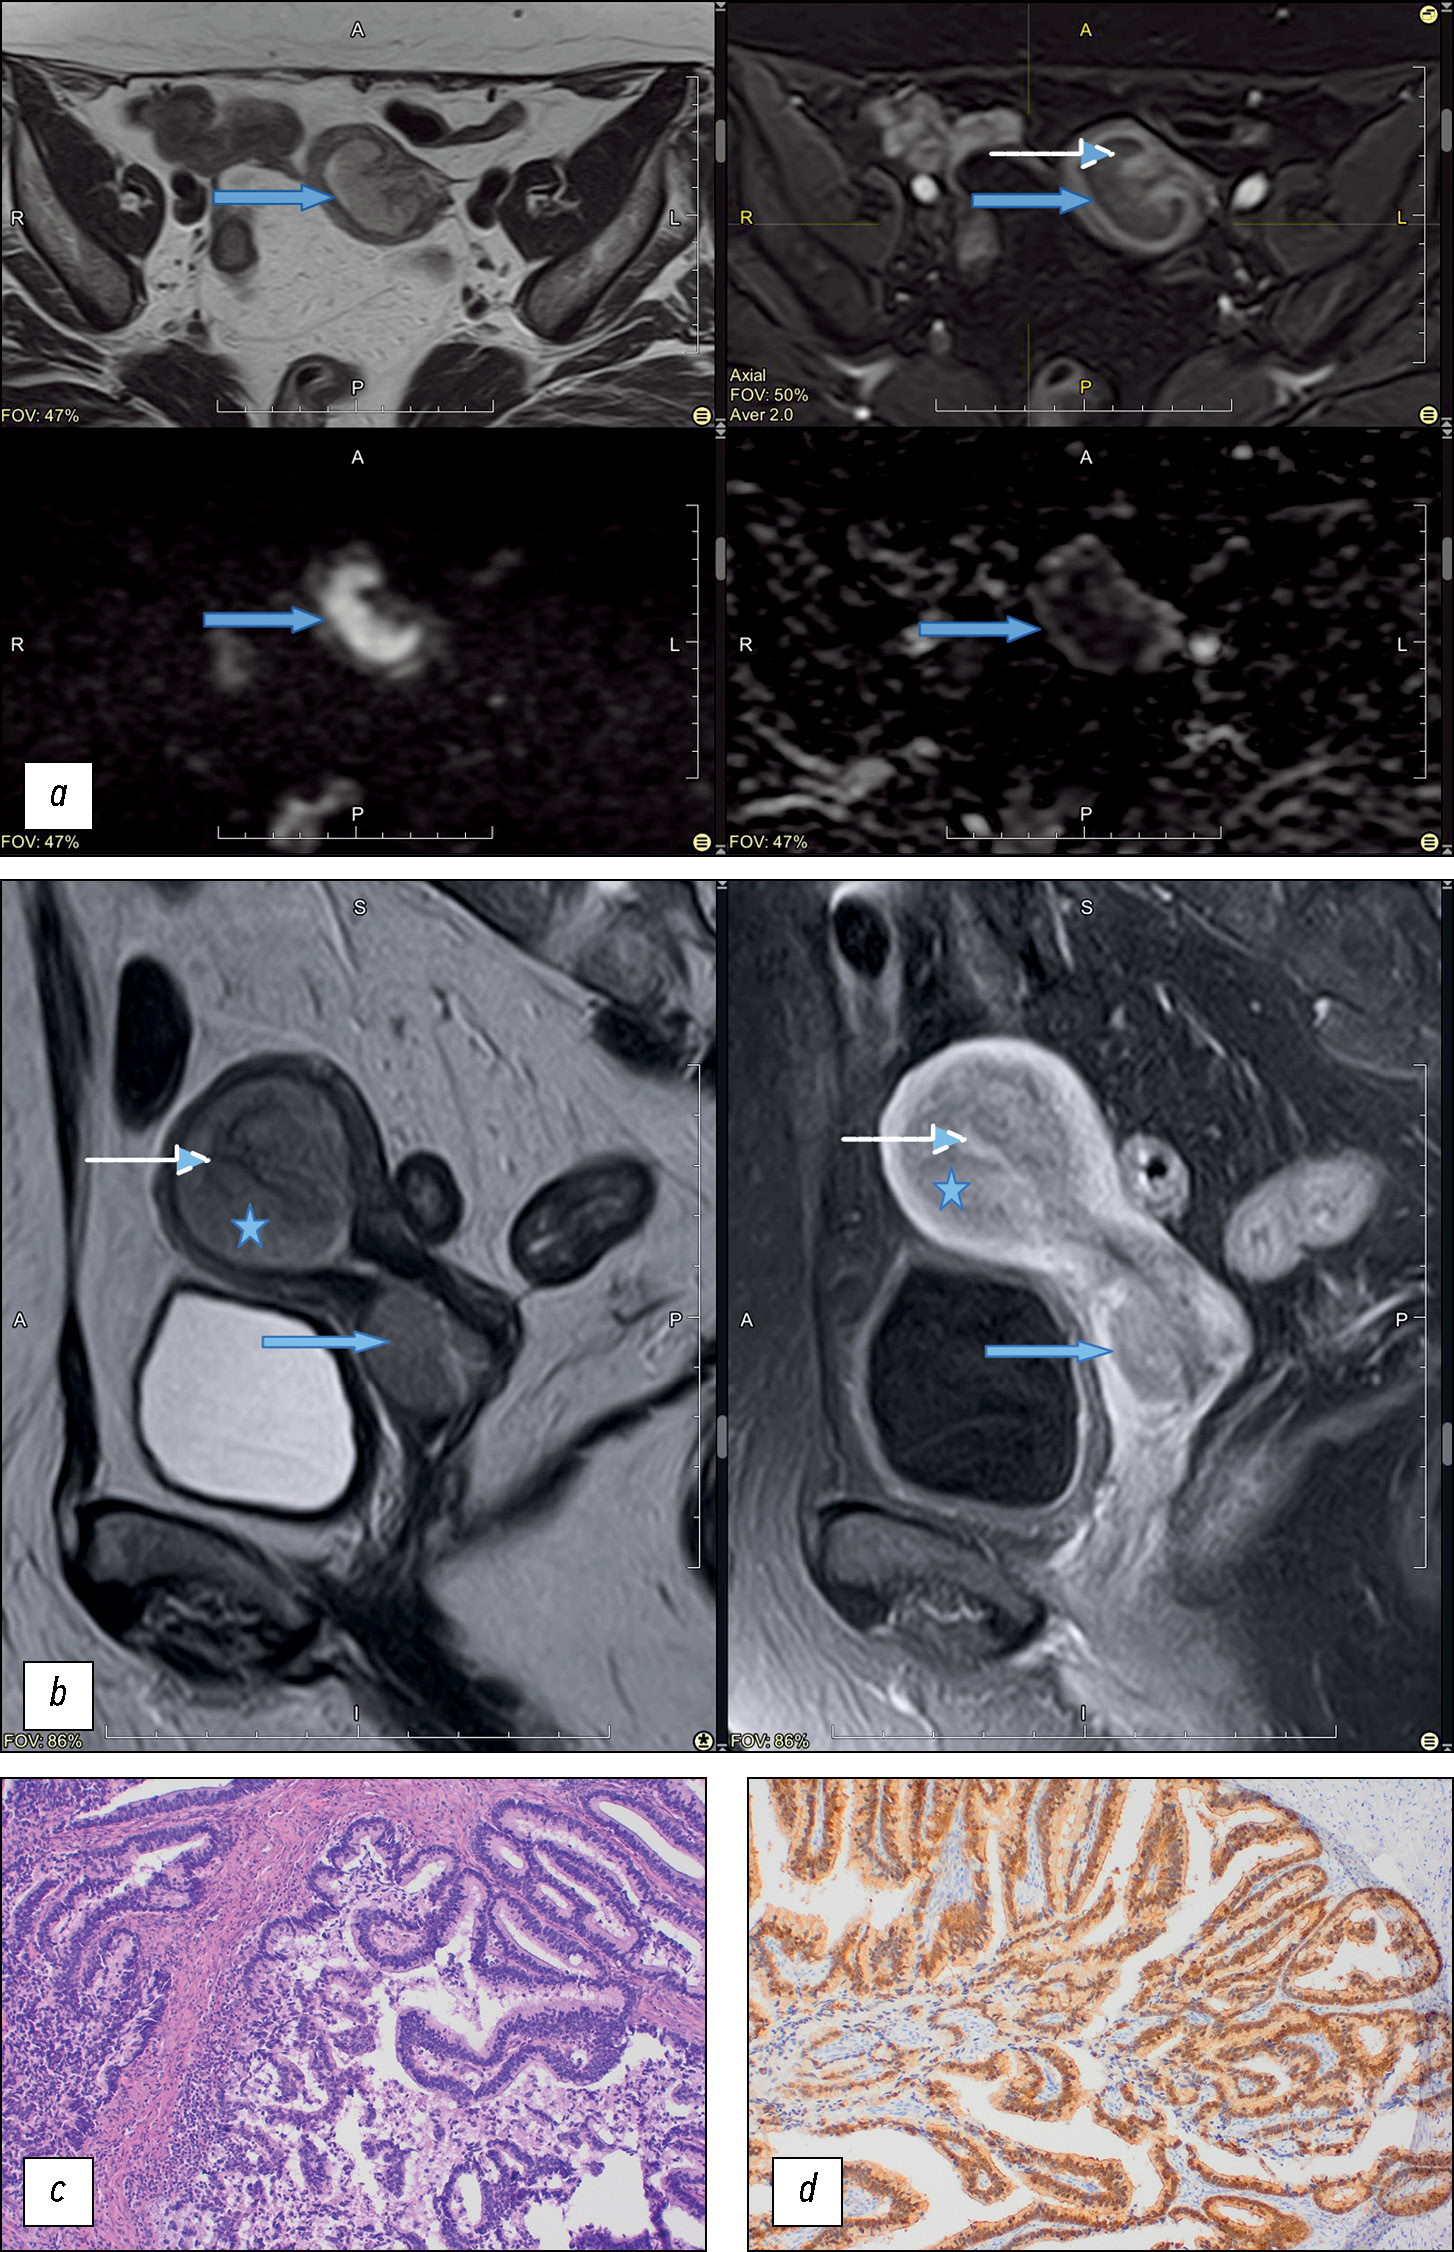

We identified two types of tumor growth in the cervical stroma: the most common were the endophytic type (75%, n = 15), characterized by diffuse enlargement and barrel-shaped cervical transformation (Fig. 3), and exophytic type, which occurred in 25% of cases in the present study (n = 5). Exophytic tumors were most commonly located in the vaginal cervix, with tumor masses prolapsing into the vagina or cervical canal lumen (Fig. 3). The exophytic tumor was represented by different histologic subtypes of CA:

- Poorly and moderately differentiated typical endocervical adenocarcinoma, 2 cases

- Poorly differentiated serous adenocarcinoma, 1 case

- Adenosquamous carcinoma, 1 case

- Endometrioid endocervical adenocarcinoma, 1 case

Fig. 3. Сervical adenocarcinoma growth pattern. The upper row of images is T2-weighted images in sagittal plane, the lower one — in axial plane.

Furthermore, endophytic tumors were characterized by different histologic types and differentiation patterns. No correlation was found for the type of tumor growth and its histologic subtype.